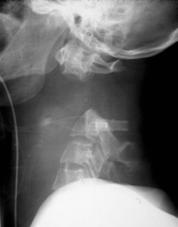

TRAUMA CERVICALA

Incidenta laterala Incidenta

laterala Incidenta

antero-posterioara

Incidenta oblica Incidenta laterala Incidenta antero-posterioara

Aspect normal Aspect normal Aspect normal